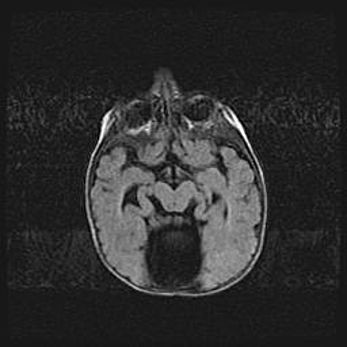

Мальформация Денди-Уокера. Киста задней черепной ямки.

Агенезия мозолистого тела.

Возраст: 2,5 месяца

Вес: 2420 г

Пол: женский

Окружность головы: 37 см

Срок гестации: 32 недели

Мальформация Денди—Уокера — редкий вид патологии ЦНС, представляющий собой врожденный порок развития каудального отдела ствола и червя мозжечка, ведущий к неполному раскрытию срединной (Мажанди) и латеральных (Лушка) апертур IV желудочка мозга. Для этогно синдрома характерна триада симптомов: гипотрофия червя мозжечка и/или полушарий мозжечка, кисты задней черепной ямки, гидроцефалия различной степени. В 70% случаев порок сочетается и с другими аномалиями головного мозга, в частности с агенезией мозолистого тела.